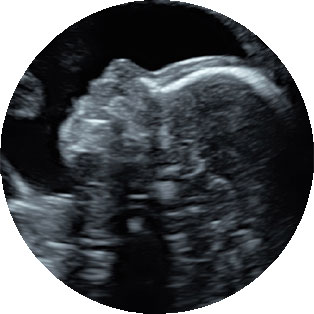

Το μέτωπο, οι οφθαλμικοί κόγχοι, τα χείλη και τα αυτιά ανευρίσκονται σταθερά μετά την 12 εβδ. Οβελιαίες, εγκάρσιες και στεφανιαίες τομές είναι αποκαλυπτικές για την εκτίμηση της ανατομίας. Η μέση οβελιαία τομή μάς δίνει το προφίλ του εμβρύου, ενώ οι παραβελιαίες που εφάπτονται στο κρανίο τα αυτιά. Ωστόσο, οι πιο σημαντικές είναι οι στεφανιαίες για την ανεύρεση όλης της ανατομίας.